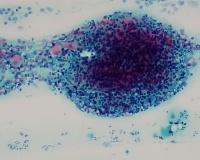

一例宫颈涂片

性别

女

年龄

59岁

一般病史

常规体检

标本类型

宫颈脱落细胞学

制片方法

涂片

染色方法

巴氏染色

淋巴滤泡性宫颈炎可能性更大一些。

这例最好结合临床病史或详细了解患者就诊史及临床有无异常症状,同意楼上意见,倾向淋巴细胞源性炎性改变,不放心可以考虑 ASC-US。